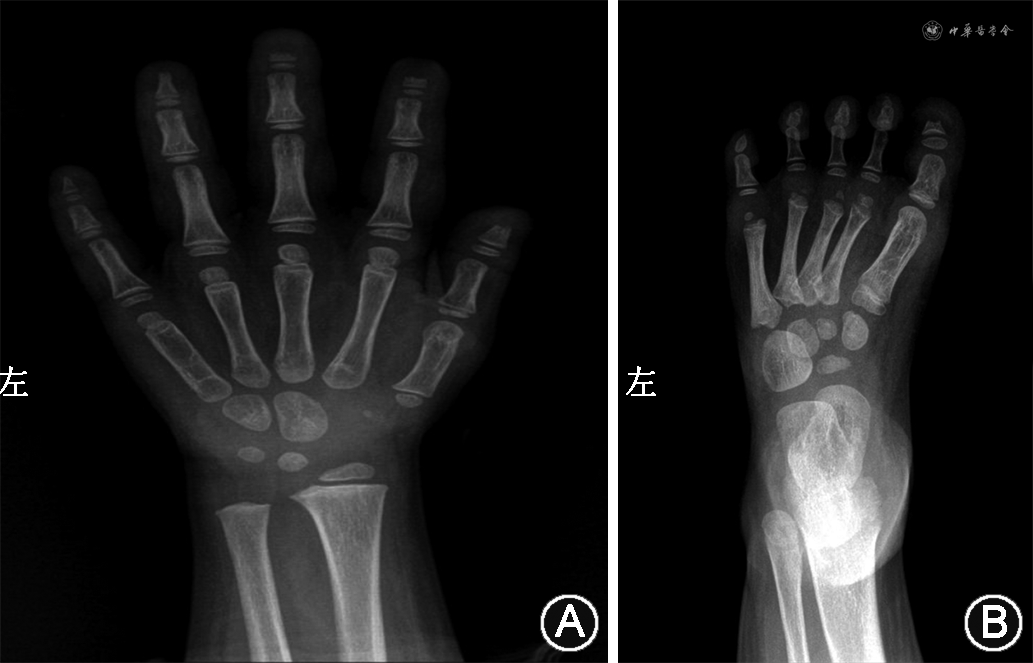

辅助检查:血常规、尿常规、肝肾功能、电解质、甲状腺功能、乙肝五项正常。生长激素激发试验示生长激素检测(空腹)1.3 μg/L;生长激素检测(30 min)4.0 μg/L;生长激素检测(60 min)9.3 μg/L;生长激素检测(90 min)9.9 μg/L;生长激素检测(120 min)3.7 μg/L,不完全缺乏。胰岛素样生长因子1 72.80 μg/L。微量元素六项示全血微量元素钙 1.60 mmol/L,镁 1.38 mmol/L,铁 7.53 mmol/L,铜 20.95 μmol/L,锌 68.86 μmol/L,铅 27.82 μg/L;甲状腺功能八项示三碘甲状腺原氨酸 2.51 nmol/L,余正常。空腹血糖 4.31 mmol/L;25-羟维生素D 67.0 nmol/L。骨密度示重度不足。心脏超声示心内结构及各心腔大小未见明显异常,左室收缩功能正常,彩色血流未见明显异常。泌尿系统超声示双肾囊肿。垂体磁共振成像示空泡蝶鞍,垂体高度约2.5 mm,垂体柄向右偏移;小脑扁桃体下疝畸形伴颅底凹陷,脊髓内异常信号影,考虑脊髓中央管扩张。胸椎、颈椎磁共振成像示Chiari畸形Ⅰ型(小脑扁桃体下疝畸形伴颅底凹陷,颈、胸段脊髓内异常信号影,考虑脊髓空洞);蝶鞍改变;胸椎多发蝴蝶椎。腕骨正位片示左腕骨5块,左腕骨龄符合3岁至3岁6月龄;左手第1~5指远节指骨部分骨质缺失,左足部X线片示第1趾末节趾骨部分骨质缺如(图1)。